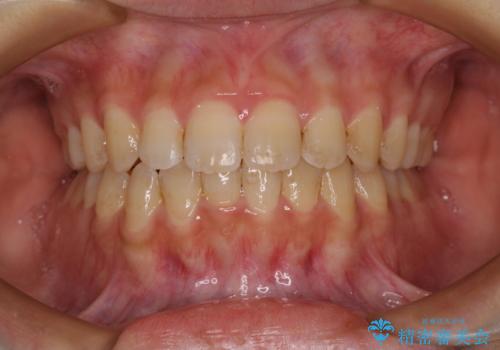

- 八重歯やデコボコをインビザラインで治療したいとのことで来院された患者様です。

インビザライン単体で治療を行うには叢生が強いと判断されたため、事前にワイヤー装置で抜歯矯正を行い、ある程度改善してからインビザラインにて仕上げていくこととしました。